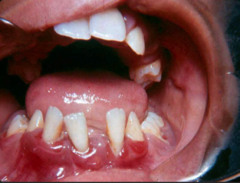

pericornitis

-Erythematous, painful, swollen tissue around the crown of a partially erupted tooth